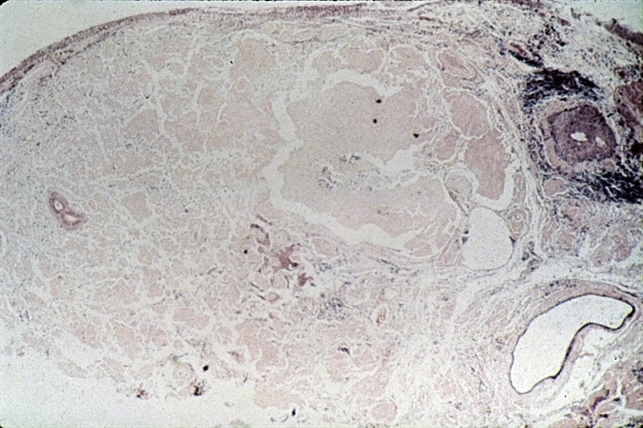

- amyloidosis, conjunctiva, acellular

- Amyloidosis of the conjunctiva showing clumps of pink, acellular material.